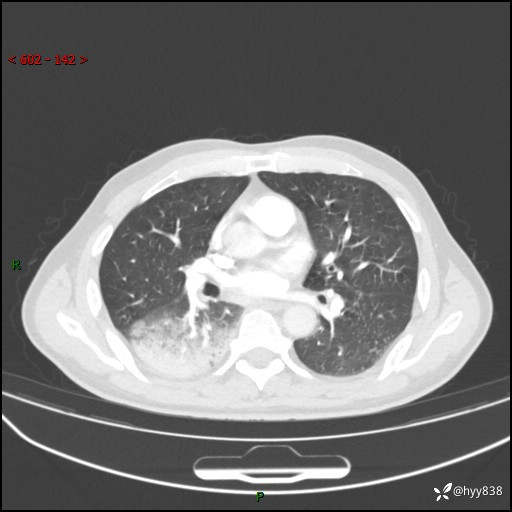

【患者信息】:63岁/男

【主诉】:发热5余天

【现病史及既往史】:患者5余天无明显诱因出现畏寒寒战发热,最高体温39.5℃,发热无明显昼夜规律,伴全身乏力、头晕,无头痛、无咳嗽咳痰、无胸痛咯血、无气短、无腹痛腹泻、无尿频尿急尿痛等不适,于当地市第五人民医院就诊,予以抗感染等治疗(具体不详)后发热无明显好转,1天前查胸部CT提示右下肺感染,为求进一步诊治,门诊以“社区获得性肺炎”收治入院; 起病以来,患者精神、食欲一般,睡眠可,大小便正常,体力体重较前无明显变化。

【检查】:胸部CT增强